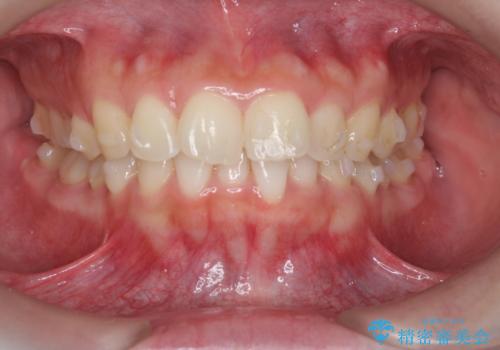

マウスピース 狭窄歯列の改善

- 噛み合わせが深い、笑った時の歯並びの改善を求めて来院されました。

マウスピース型の矯正装置インビザラインを用いた治療を計画します。

狭くなってしまった歯並びを放物線状に並べることで噛み合わせの安定・見た目の改善・ガタつきの改善を達成することができました。